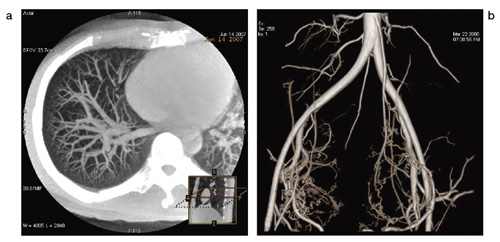

■ 高精細3D 画像をフルオート,高速再構成

本装置においては,FPDを秒間40°の回転速度で200°の範囲を回転させ,毎秒30フレームの画像を撮影することによりコーンビームCT(CBCT)が撮影可能であり,直径約25cm,高さ約25cmの円筒形のボリュームデータを獲得することができる(図2 a)。

Innova3Dは回転データ収集後,画像転送から3D画像表示までをフルオートで行え,複雑な血管の走行を立体的に把握することが可能なアプリケーションである(図2 b)。栄養血管の特定を短時間で行うことができ,検査時間,被ばく,造影剤使用量の削減にもつながる。

図2 CBCT(a)とInnova3D(b)